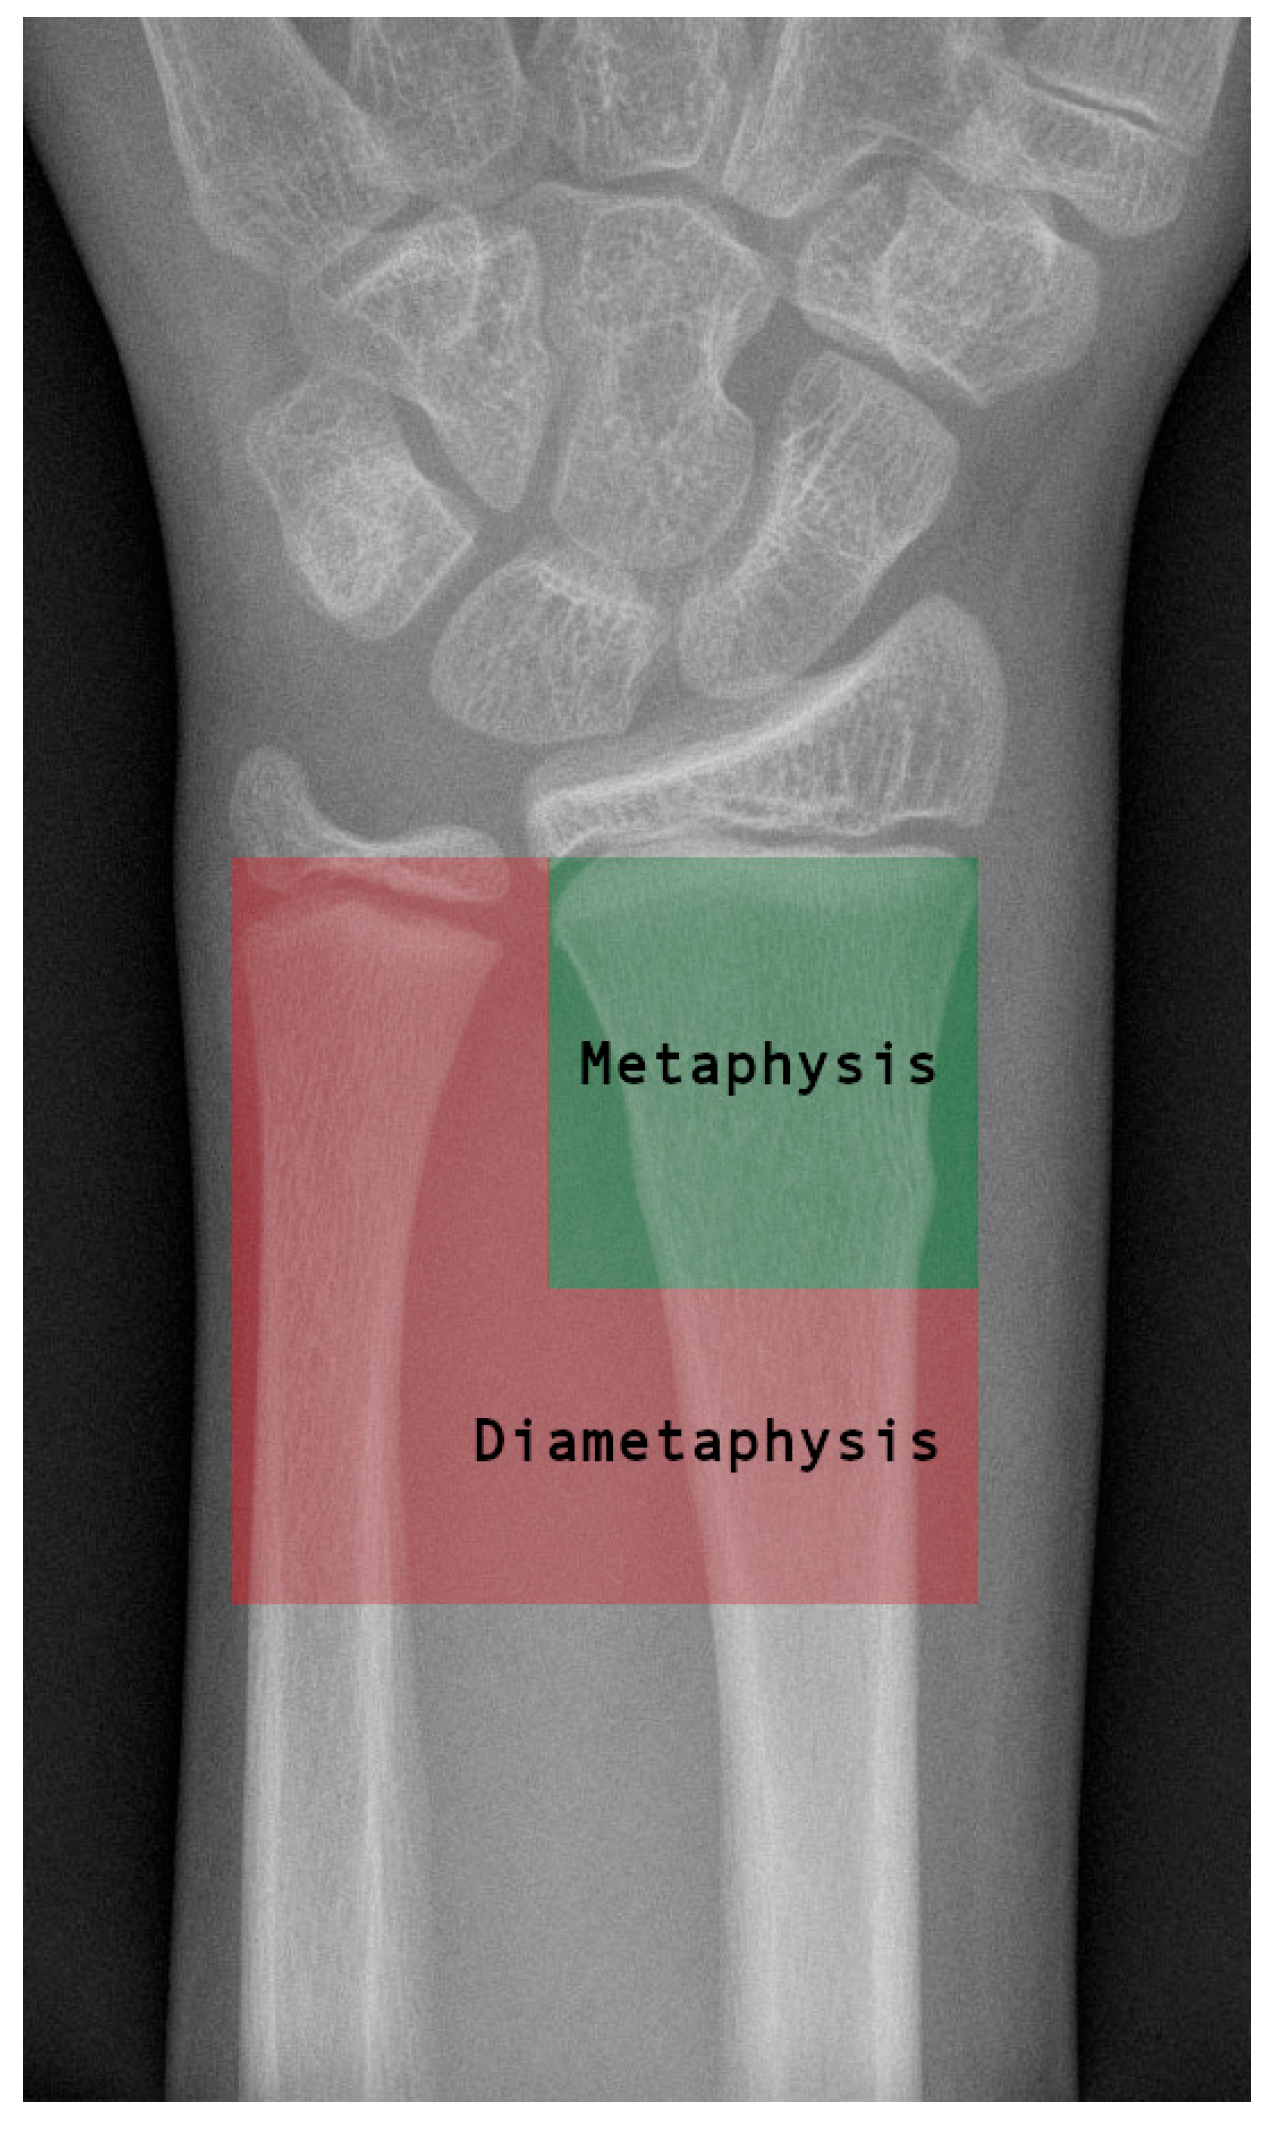

Plate and K-Wire Show Advantages to Nailing for Distal Diametaphyseal Radius Fracture in Children: A Retrospective, Two-Center Study

1. Introduction